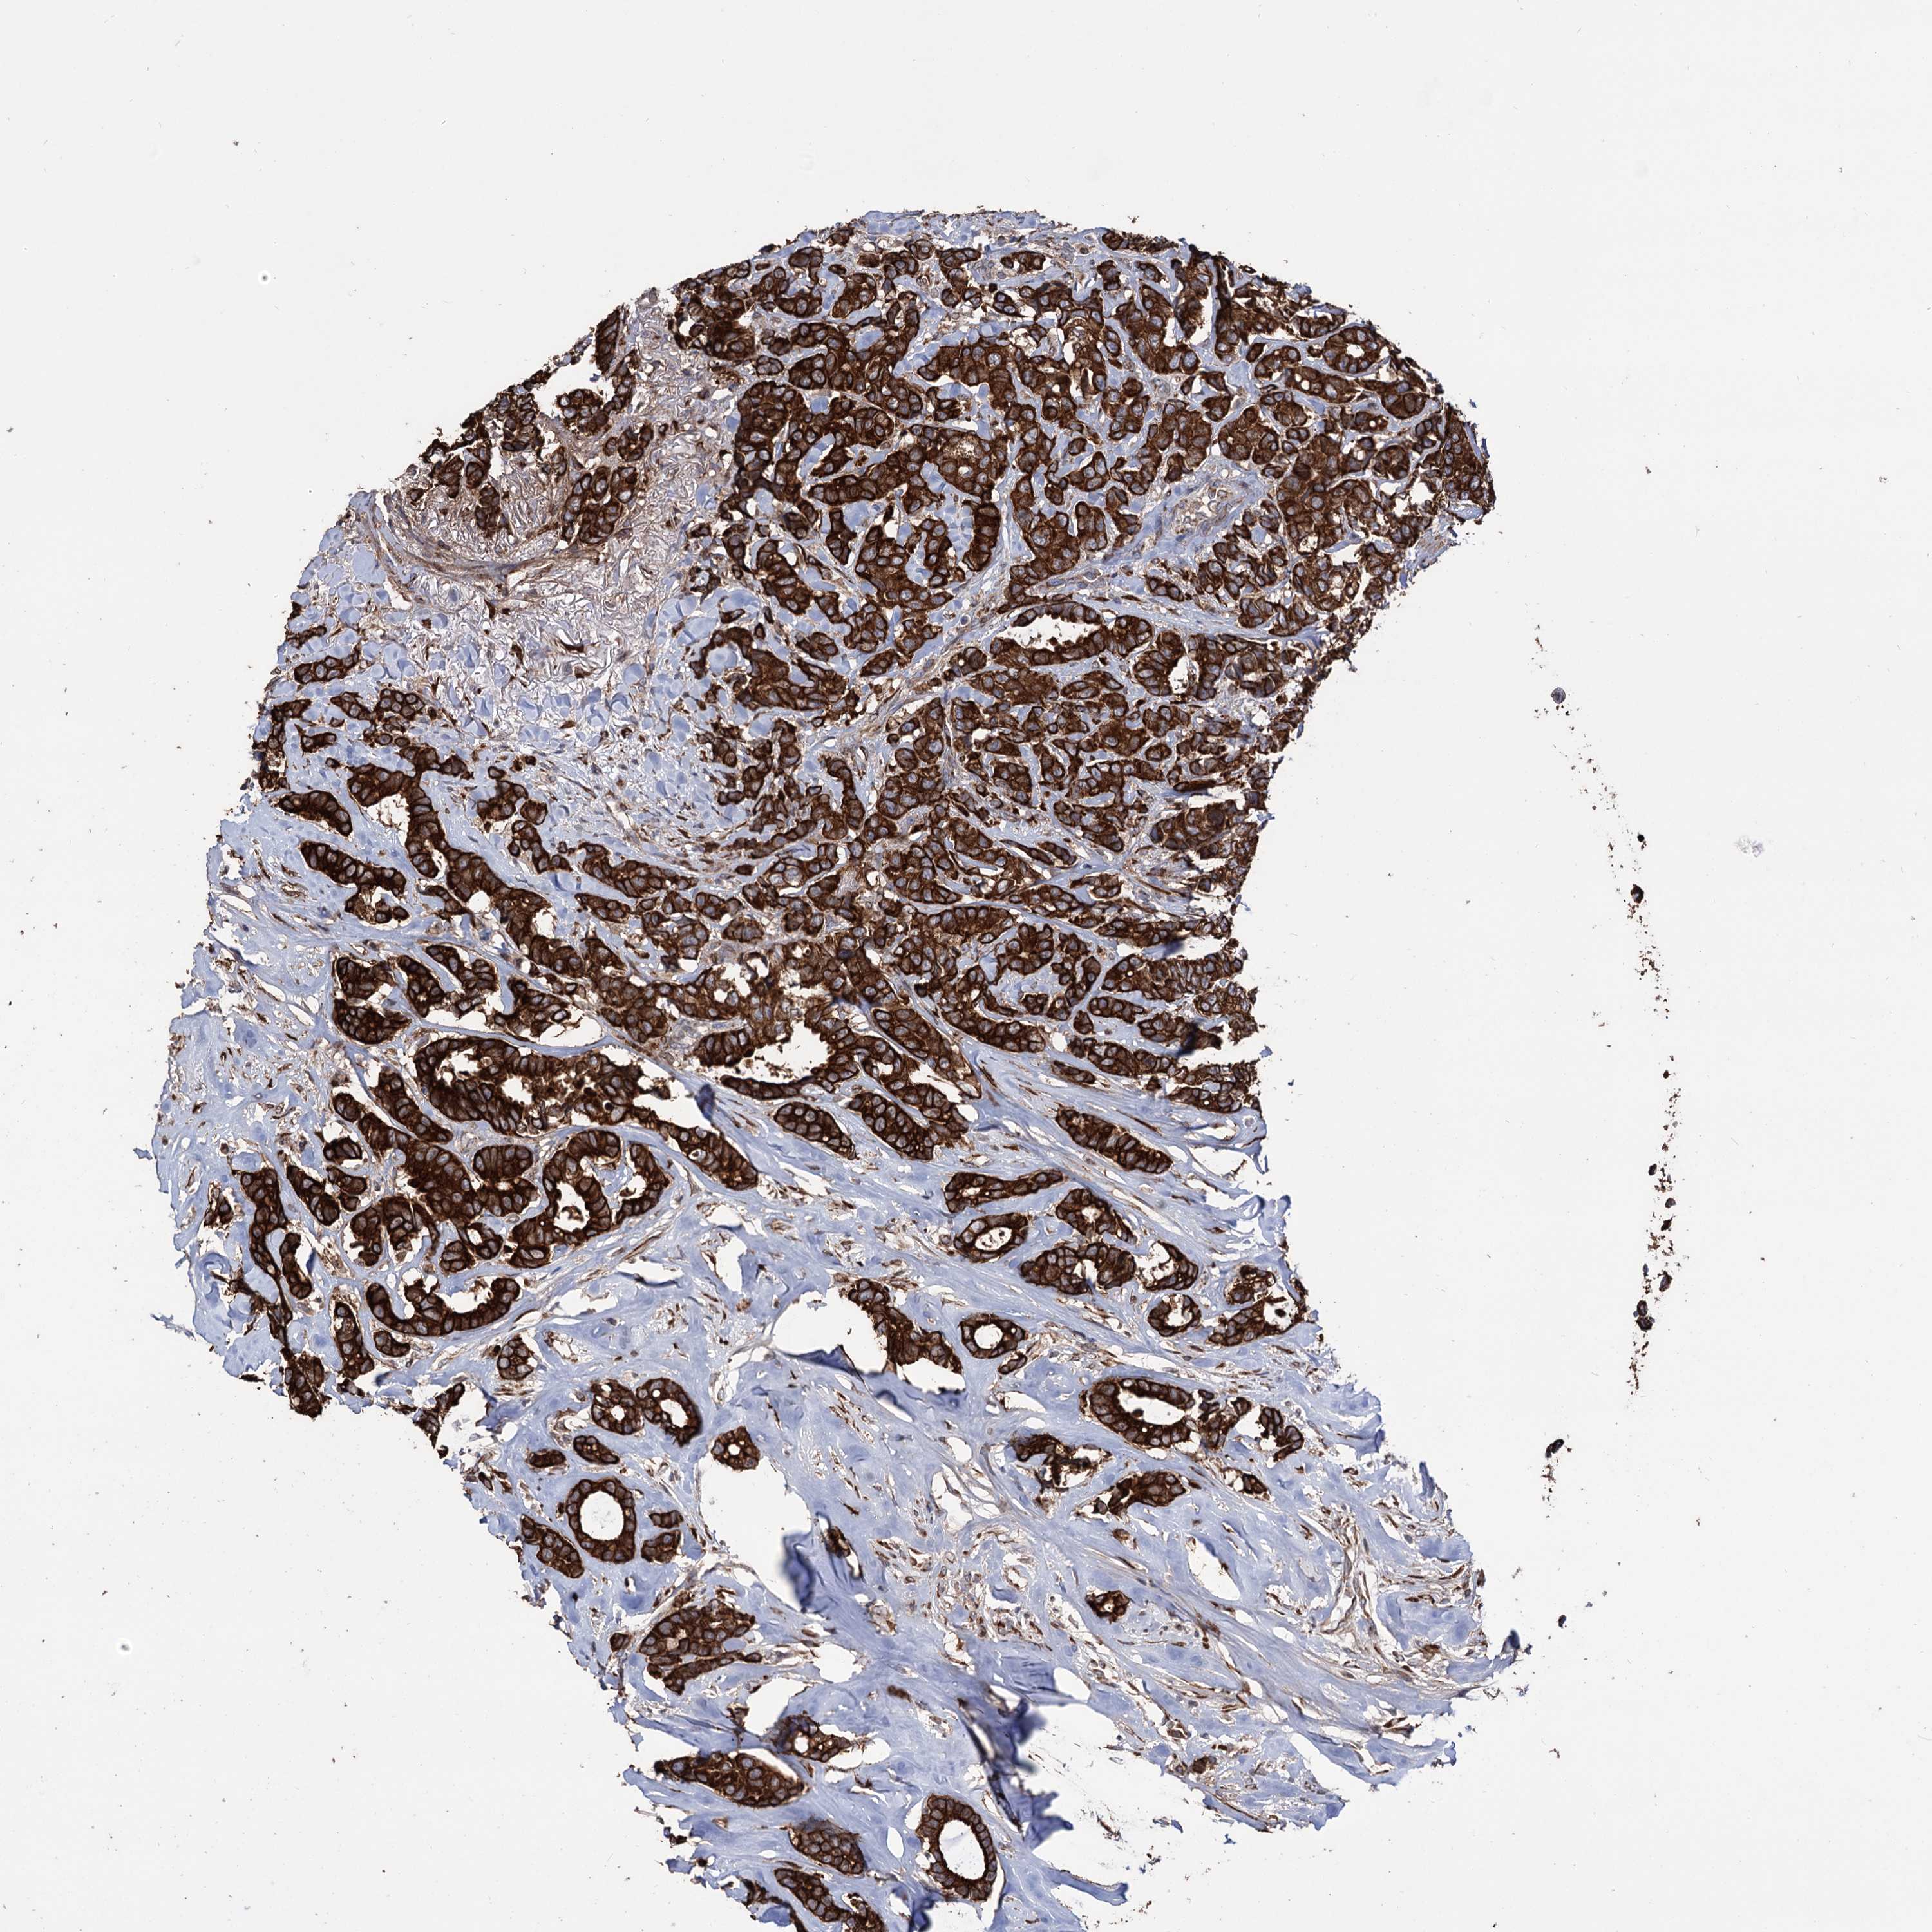

CANCER BREAST CANCER Show tissue menu

BRCA TCGA BRCA VALIDATION PROTEIN EXPRESSION